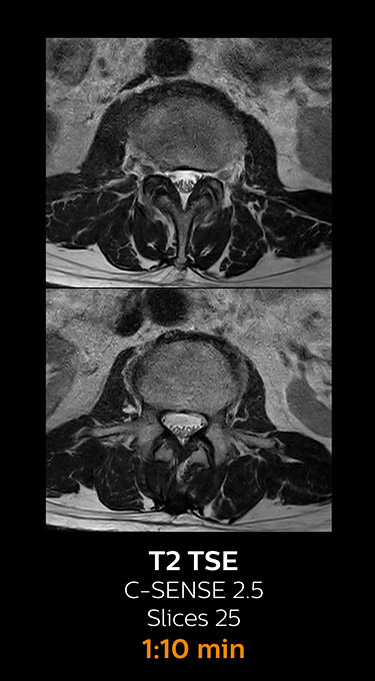

Fast MRI of lumbar spine

With Compressed SENSE, the scan time for the routine lumbar spine examination at KNC was reduced from 11:41 to 8:17 minutes,

which corresponds to 34% reduction.

MRI examination of lumbar spine with Compressed SENSE

MRI examination of the lumbar spine with Compressed SENSE

Ingenia 3.0T CX

Scan time 8:17 min. (was 11:41 min. without Compressed SENSE)